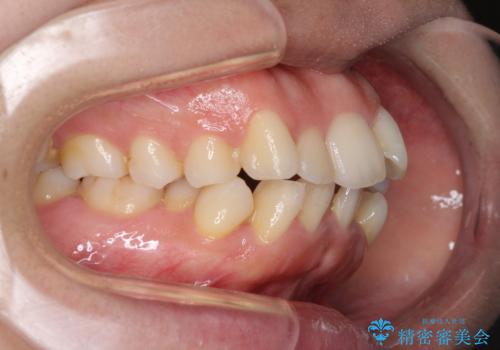

- 前歯のデコボコと口元の突出感を気にして来院された患者様です。

上下左右第一小臼歯4本を抜歯し、ワイヤー装置にて口元を引っ込めるよう矯正治療を行うこととしました。

叢生が強かったため、口元の突出感の改善には限界がありましたが、横側からも口元が引っ込んだ感じが分かるほど改善されました。